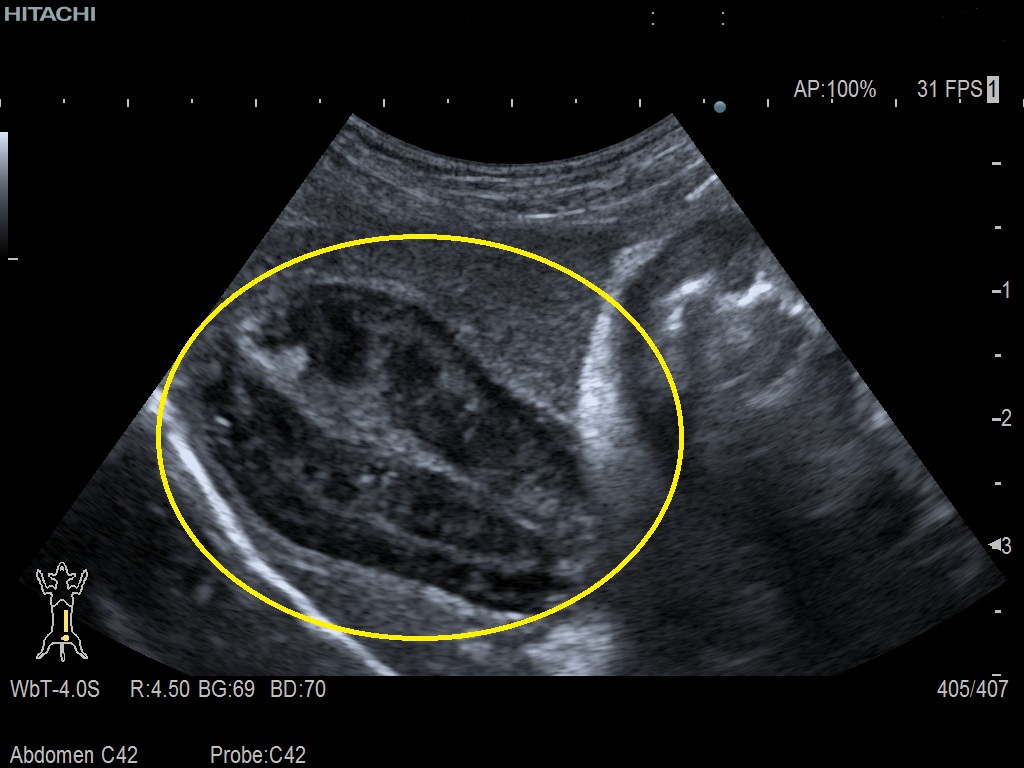

腹部超音波検査にて以下の所見を認めました。

- 胆嚢内にゼリー状内容物が充満

- 典型的な胆嚢粘液嚢腫所見(黄丸)

- 腹水の貯留を認めました。

胆嚢粘液嚢腫は胆汁がゼリー状に固まり胆嚢内に充満する疾患です。